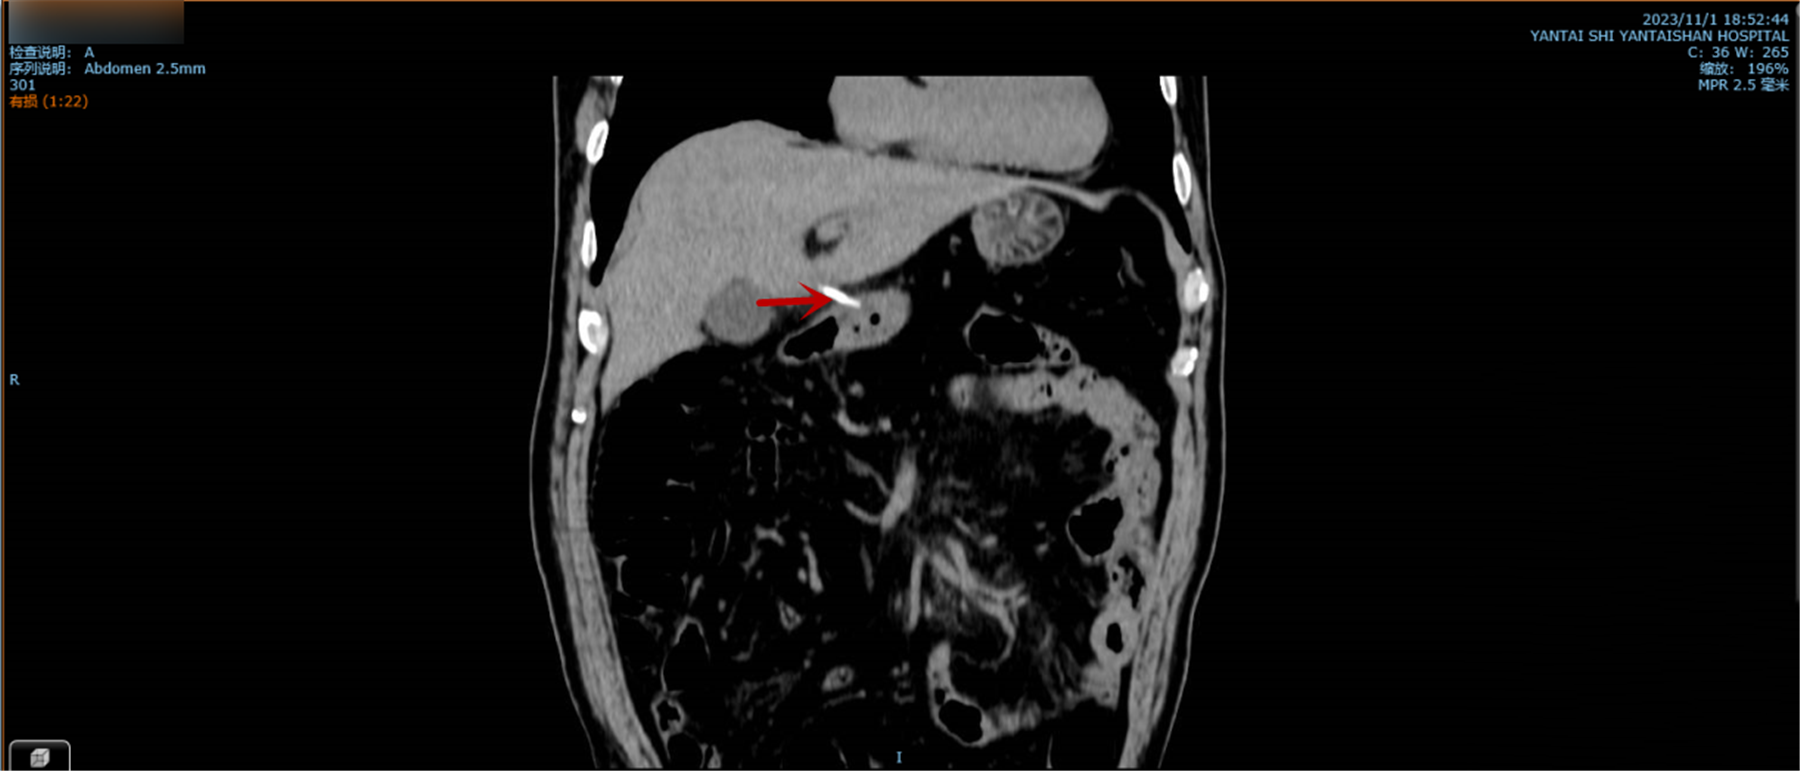

图中所示为李先生吞入腹中的鱼刺。

刚吞入鱼刺时,李先生并无异样感受,此后出现了剧烈腹痛并高烧,他便到当地医院就诊,CT检查提示:胃窦及十二指肠处条状高密度致密灶并突向腔外与肝脏相贴紧密,两端与胃壁及肝脏分界不清,提示异物并穿孔可能。当地医院建议李先生接受常规手术治疗,他不能接受开刀手术带来的瘢痕,便婉拒了医生的建议。后经多方打听,得知烟台山医院东院胃肠外科可行微创手术治疗,随即连夜赶往,王永副主任医师接诊后结合患者病情、辅助检查及患者诉求,制定了“双镜”联合的手术方案——先行胃镜检查,如能取出异物最好,如不能取出异物也能明确胃内损伤情况以及损伤部位,为后续治疗提供有力支持;不能直接取出时,则行腹腔镜探查术。该手术方案为微创术式,能最大程度上减小手术切口带来的瘢痕、降低手术创伤、减轻患者疼痛,李先生听后,欣然同意此方案。

完善术前准备后,王永团队医生急行胃镜检查,仔细探查全胃,未发现鱼刺及其他异物,但见胃窦水肿以前壁为著,结合术前CT检查,考虑异物可能已从胃窦前壁穿出,再次探查全胃一圈未见其他异常后决定行腹腔镜探查术。术中,医生在李先生的胃窦前壁发现了一根长约5厘米的鱼刺,它已穿透胃窦,刺入肝脏,此后在腹腔镜直视下完整地取出鱼刺并缝合胃窦穿孔。后经治疗,李先生很快康复出院。